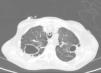

En la Rx tórax se observaron tractos fibrocavitados en ambos campos superiores y signos de atrapamiento aéreo que confirmó la TAC (fig. 1). No se objetivaron anomalías destacables en cráneo ni abdomen. Se realizó una fibrobroncoscopia en la que se objetivaron signos de inflamación de la mucosa bronquial y se tomaron muestras de aspirado bronquial para cultivo convencional y micobacterias. En el cultivo convencional se observó crecimiento de flora saprofita y no se obtuvo crecimiento de Legionella spp ni de hongos. En la tinción de Ziehl-Neelsen no se observaron bacilos ácido-alcohol resistente (BAAR). Se realizó estudio serológico frente al VIH y anticuerpos IgM frente a Mycoplasma pneumoniae, Coxiella burnetii, Chlamydophila pneumoniae, Legionella pneumoniae e IFI frente a Chlamydophila psittaci con resultado negativo. Los hemocultivos y el Mantoux también resultaron negativos.